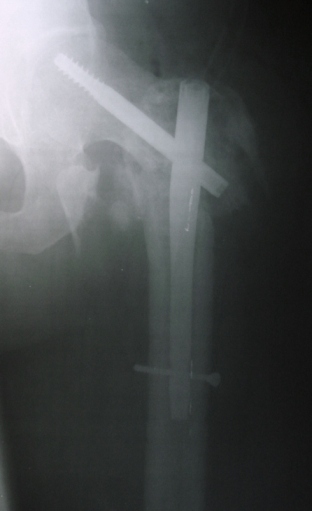

[Ortho] Реостеосинтез?

Александр Николаевич, вот, что удалось сегодня выдавить из Армана. С

аксиальным никак, расскажи, пожалуйста,  по-подробнее про укладку с

согнутыми ногами - я такую не знаю (сгибать обе? куда кассету?).